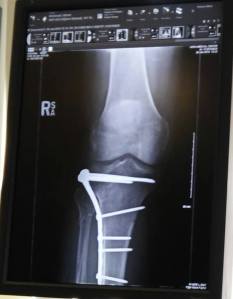

my leg xrays 3-24-2016 On March 26, 2016 By Michel McDonald Share this: Email a link to a friend (Opens in new window) Email Print (Opens in new window) Print Share on Reddit (Opens in new window) Reddit TweetShare on TumblrLike Loading...